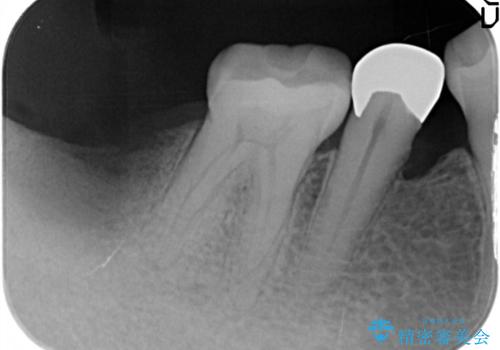

- 奥歯が痛いことを主訴に来院されました。

重度の歯周病により保存困難と診断し、抜歯後にインプラント治療を行いました。

抜歯後十分な骨の回復が認められず、単独の骨増生を行った後にインプラントを埋入しました。

インプラント埋入時に骨が足りない場合にはインプラント埋入前に骨増生を行います。また、インプラント周囲の角化歯肉が不足した場合は角化歯肉の移植も行うことがあります。

どちらの治療もインプラントの長期予後を高めるために必要な治療です。